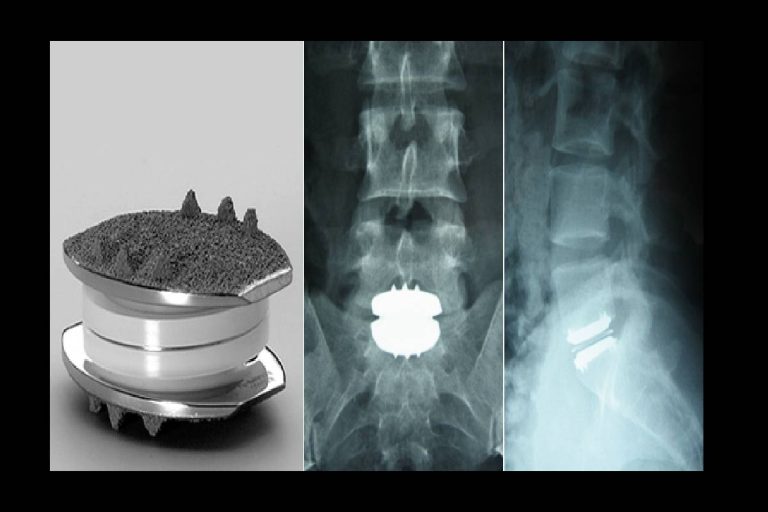

Can Vertebral Discs Be Replaced . In lumbar artificial disk replacement, worn or damaged disk material between the small bones in the spine (vertebrae) is removed and replaced with a prosthetic, or artificial disk. Lumbar disc replacement is an alternative to spinal fusion. In a spinal fusion procedure, a damaged disc can be removed and replaced with a bone graft to stimulate bone growth. Disk replacements can be performed in the cervical and lumbar spine and, if necessary, several replacements can be done in one operative procedure. The spine is made up of small bones called vertebrae that are separated by tough discs that sit between the bones and act like cushions. Depending on which disk or. The goal of artificial disc replacement is to. If your pain comes from the discs this can be achieved by removing the disc completely and replacing it with an artificial disc or by fusing. This surgery consists of replacing the painful spinal disc with a device designed to mimic the disc’s natural movement. Over time, the space of the absent disc gradually fills.

The spine is made up of small bones called vertebrae that are separated by tough discs that sit between the bones and act like cushions. Disk replacements can be performed in the cervical and lumbar spine and, if necessary, several replacements can be done in one operative procedure. Lumbar disc replacement is an alternative to spinal fusion. This surgery consists of replacing the painful spinal disc with a device designed to mimic the disc’s natural movement. Over time, the space of the absent disc gradually fills. The goal of artificial disc replacement is to. If your pain comes from the discs this can be achieved by removing the disc completely and replacing it with an artificial disc or by fusing. In lumbar artificial disk replacement, worn or damaged disk material between the small bones in the spine (vertebrae) is removed and replaced with a prosthetic, or artificial disk. In a spinal fusion procedure, a damaged disc can be removed and replaced with a bone graft to stimulate bone growth. Depending on which disk or.